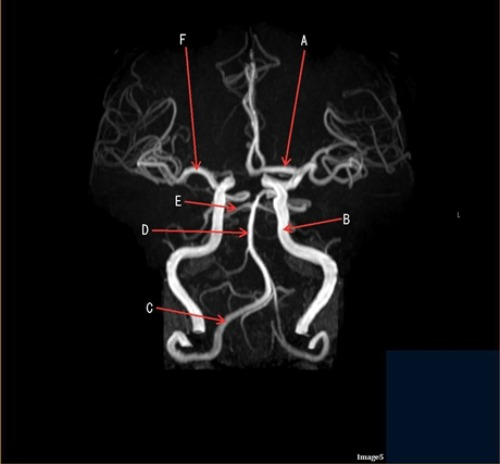

Letter F in Image 5 is pointing to:

A. Anterior cerebral artery

B. Internal carotid artery

C. Basilar artery

D. Posterior cerebral artery

E. Middle cerebral artery

Letter C in Image 5 is pointing to:

A. Vertebral artery

Letter D in Image 5 is pointing to:

Letter A in Image 5 is pointing to:

Letter E in Image 5 is pointing to:

Image 5 is an example of an:

A. MRI brain

B. MRV sagittal sinus

C. MRS single Voxel

D. MRA Circle of Willis

Letter B in Image 5 is pointing to:

B Internal carotid artery